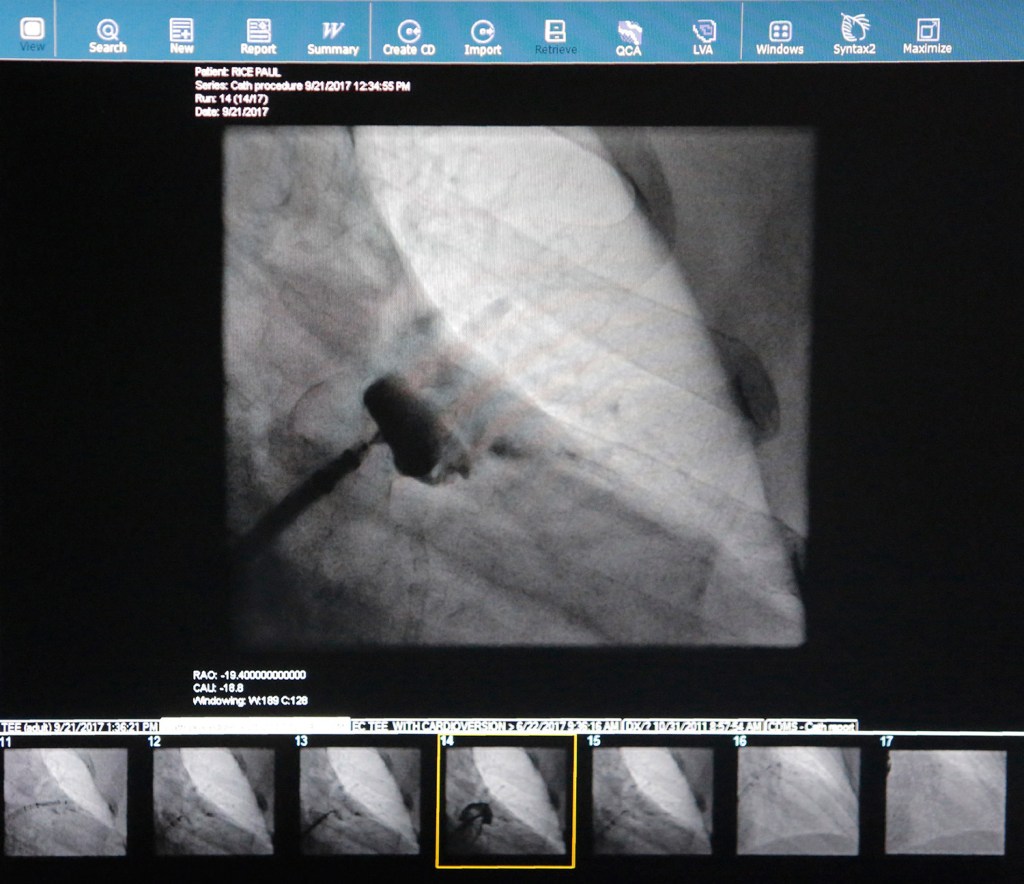

Rice lay on the operating table in late September for the procedure, but it didn’t look like a scene from “M*A*S*H” or “Grey’s Anatomy,” as there was a minimal amount of blood. A team of 10 doctors, nurses, medical professionals and representatives from Boston Scientific helped out.

A small incision was made above Rice’s right hip, and doctors snaked in a tube. Inside the tube they inserted the Watchman, and the device was attached to a long, skinny metallic piece that was used to journey through the femoral artery to the heart.

Corsello was the lead surgeon for the day, and he worked with Dr. Jay Powers and Dr. Samip Vasaiwala on the tasks of carefully working the device to exactly the right spot where it would hook into the sides of the appendage. The doctors would constantly look at ultrasound monitors to see how the device – made out of nickel titanium and polyester fabric – was doing.

Powers’ job was to scrutinize the ultrasound images and guide Corsello and Vasaiwala to where they needed to go.

Corsello said they had one small hiccup, where the sheath they used did not bend enough to get to the appendage. They had to remove the sheath, get one that bent slightly and try again.

Eventually, better imaging and 3-D models will enable surgeons to practice on an exact replica of each patient’s heart before doing the surgery, eliminating complications presurgery. Doctors now look at ultrasounds and prepare for the surgery by measuring where the device should go and how big it should be. Rice’s Watchman was 24 millimeters.

Despite having to reinsert the sheath, the surgery only took about 90 minutes.

“Yeah, that looks really good there,” Corsello said, peering at the screen.

A counterclockwise turn, and the Watchman was released and implanted.

“The device is deployed,” Corsello said, signaling the surgery was completed, before removing his scrubs.